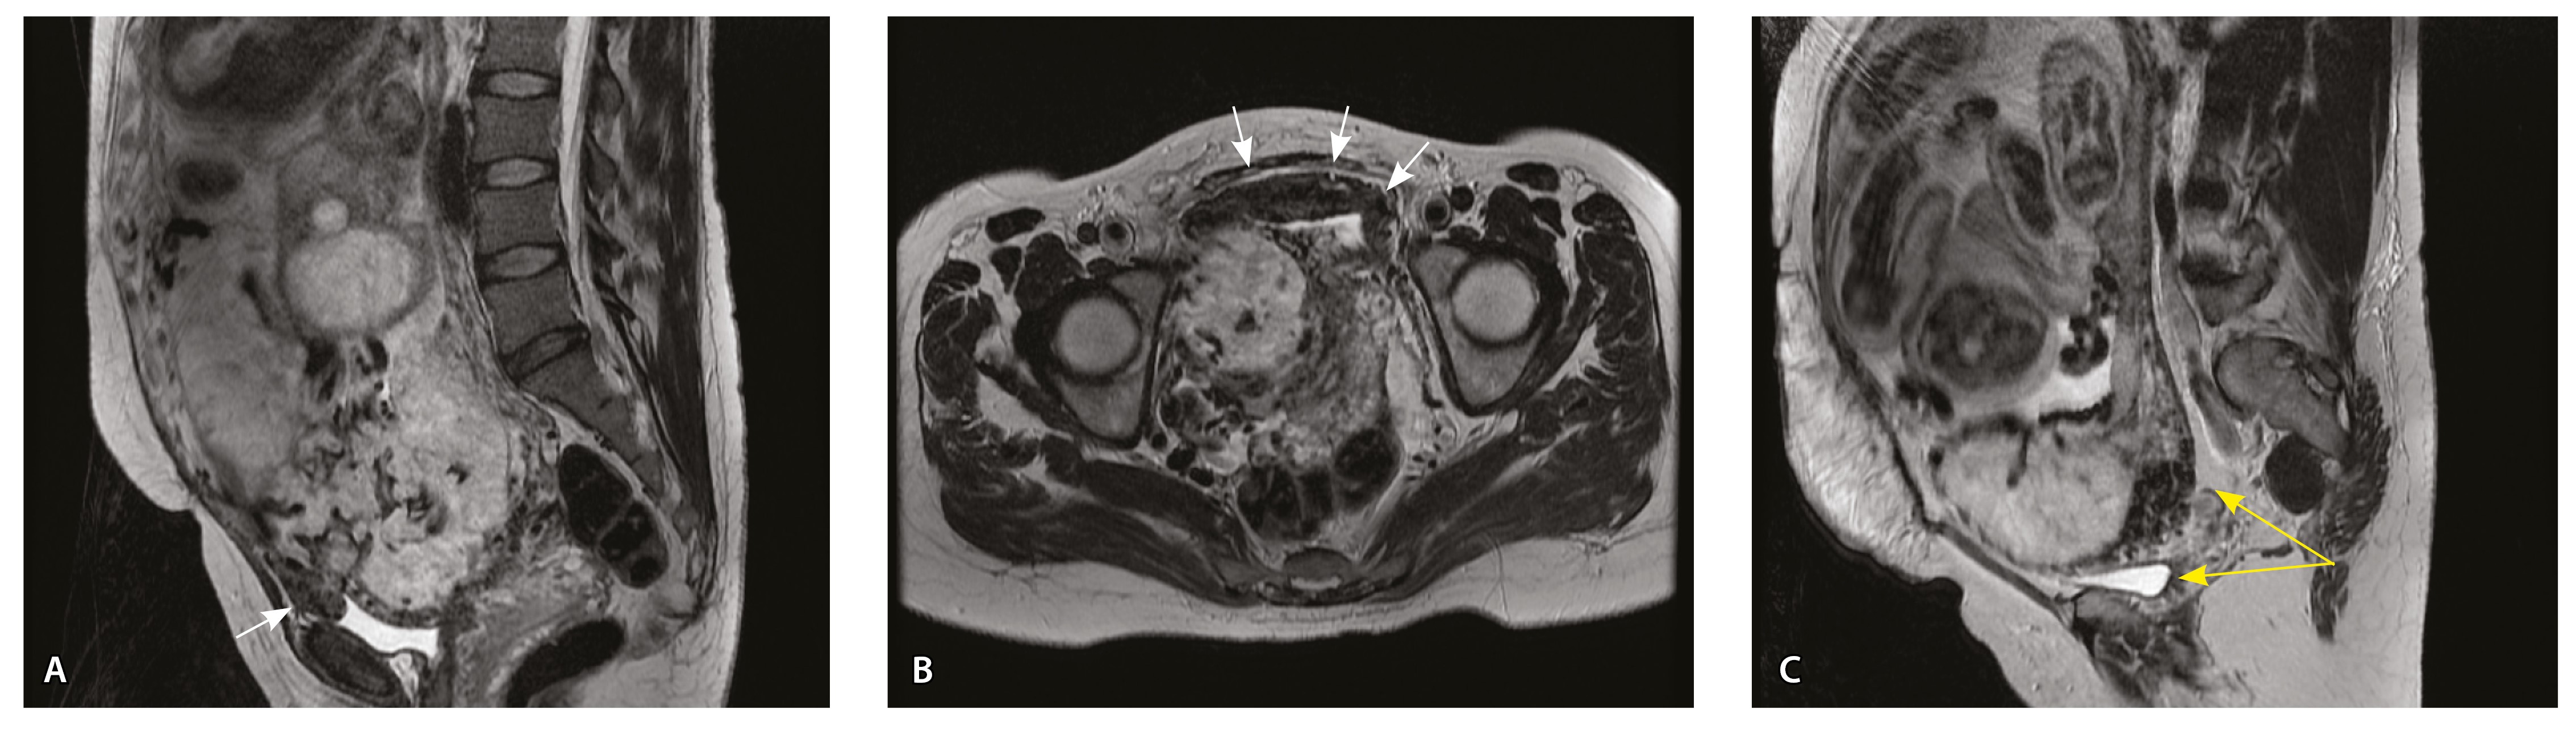

Сосуды 2-го типа. Единичные сливающиеся сосудистые полости в маточно-плацентарной области, мелкие ретроплацентарные гематомы, участки с белковым содержимым по МР-сигналу в зоне контакта ворсин со стенкой матки (рис. 4).

Рис. 4. Беременность 32 недели, pl. accreta, PAS 1 по FIGO. На магнитно-резонансных томограммах в режиме Т2-взвешенного изображения в сагиттальной (А) и аксиальной (Б) плоскостях видны сосуды на границе маточно-плацентарной области, сливающиеся между собой (белые стрелки), без выраженного дефицита толщины миометрия и рубца от кесарева сечения, без признаков выбухания стенки матки. На Т1-взвешенном изображении в режиме подавления сигнала от жировой ткани в аксиальной плоскости (В) выявляется наличие участков повышенного сигнала (желтые стрелки) на границе маточно-плацентарной области, что соответствует геморрагическому компоненту в подострой/хронической стадии (ретроплацентарные гематомы) либо белковому содержимому (фибриноид)

Непосредственное сравнение МР-картины с операционным материалом подтвердило, что полости с геморрагическим компонентом соответствовали ретрохориальным гематомам различной давности, чаще подострой и хронической стадий, которые состояли из гемолизированных эритроцитов, нитей фибрина сетчатого строения, а также замурованных атрофичных ворсин (рис. 5). Следовательно, констатация на МРТ фиксированных геморрагических полостей в маточно-плацентарной области отражает не гиперваскуляризацию стенки матки, а наличие ретрохориальных гематом в подострой/хронической стадии, что следует учитывать в клинической практике.

Рис. 5. Сосуды 2-го типа при гиперваскуляризации стенки матки при патологической инвазии: А – организованная ретрохориальная гематома в маточно-плацентарной области, в ее составе много инволютивных якорных ворсин (окраска по Маллори; × 100); Б – в составе гематомы видна пролиферация цитотрофобласта (иммуногистохимическое исследование, маркер цитокератин 8; × 100)

Как видно на рис. 6, сосуды 2-го типа не встречались в норме и при плотном прикреплении плаценты (gr 2), с одинаковой частотой наблюдались при pl. accreta (gr 3) и pl. increta (gr 4) и были обнаружены у 94,4% пациенток с pl. percreta (gr 5) (р < 0,001, хи-квадрат Пирсона).

Рис. 6. Частота встречаемости сосудов 2-го типа при различной глубине приращения плаценты (grade МАPI-RADS)

Сосуды 3-го типа. Внутриматочная гиперваскуляризация с дефицитом толщины миометрия, преимущественно сосуды срединного слоя, аналог pl. increta PAS 2, гестационная перестройка радиальных артерий (рис. 7).

Рис. 7. Беременность 34 недели, pl. increta, PAS 2 по FIGO. На магнитно-резонансных томограммах в режиме Т2-взвешенного изображения в сагиттальной (A, Б) и фронтальной (В) плоскостях определяется внутриматочная гиперваскуляризация с наличием многочисленных сливающихся сосудов в толще стенки матки, в области плацентарной площадки (белые стрелки); в нижнем маточном сегменте – выраженное истончение стенки матки, рубца от кесарева сечения с формированием маточной грыжи (желтые стрелки)

При pl. increta наличие патологических сосудов на изображениях МРТ связано с неполной гестационной перестройкой радиальных артерий, расположенных в срединном слое миометрия. Так, при окраске по Маллори они определяются как сжатые комплексы артерий среднего калибра, с частичным замещением внутренних слоев стенки матки, темно-красными фрагментами плодного фибриноида. На серийных срезах видно, что в этой артерии присутствует достаточное количество инвазивного цитотрофобласта (маркер цитокератин 8), но предыдущий срез подтверждает замещение мышечной оболочки фиброзной тканью как в стенке радиальной артерии, так и в периартериальном пространстве (рис. 8).

Рис. 8. Сосуды 3-го типа при гиперваскуляризации стенки матки при патологической инвазии. Внутриматочная гиперваскуляризация с дефицитом толщины миометрия, наличием рубцовой ткани, недостаточная гестационная перестройка радиальных артерий (аналог pl. increta, PAS 2 по FIGO). А – неполная гестационная перестройка радиальной артерии в составе миометрия (окраска по Маллори; × 50); в верхней части просвета артерии виден слой фибриноида, замещающего эндотелий, такой же фрагмент – в нижней части артерии (стрелка); Б – серийный срез той же радиальной артерии с визуализацией инвазирующего цитотрофобласта (маркер цитокератин 8; × 50); В – серийный срез той же радиальной артерии, при окраске на выявление эластических волокон видна полная дезорганизация эластического каркаса вместо нормальных внутренней и внешней эластических мембран, результат действия инвазирующего цитотрофобласта (окраска по Вейгерту; × 50)

При анализе частоты встречаемости сосудов 3-го типа в зависимости от степени приращения плаценты (рис. 9) отмечается преобладание данного типа сосудов при глубоких вариантах инвазии плаценты – pl. increta (gr 4), pl. percreta (gr 5) – и отсутствие их при плотном прикреплении плаценты (gr 2) и поверхностном приращении (pl. accretа, gr 3) (р < 0,001, хи-квадрат Пирсона).

Рис. 9. Частота встречаемости сосудов 3-го типа при различной глубине приращения плаценты (grade МАPI-RADS)